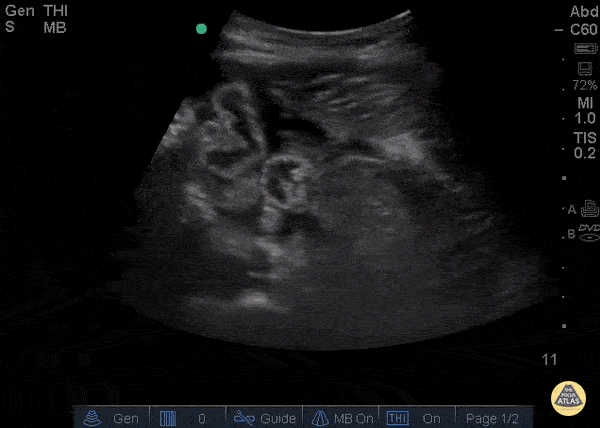

Bowel-GI - Free Fluid and Collapsed Bowel

23 year old male with no known medical history s/p surgery for sigmoid volvulus presenting with severe lower mid-abdominal pain. Ultrasound showed trace free fluid and significant collapsed bowel with no peristalsis. CT scan findings were equivocal to our US findings. Patient was found to have bowel dehiscence in the operating room. Bowel wall is most easily seen when there is free fluid or ascites. Normal bowel has layered appearance, easily compressible with intermittent peristalsis. The most frequent pathological findings found by ultrasound is wall thickening, mucosal abnormalities, the absence of peristalsis (1). One benefit of point-of-care intestinal ultrasound is decision for early surgery. Sonographic findings suggesting a need for surgery include; intraperitoneal free fluid, bowel wall thickness of more than 4 mm, and decreased or absent peristalsis (2). Valette PJ, Rioux M, Pilleul F, Saurin JC, Fouque P, Henry L, Eur Radiol. 2001; 11(10):1859-66. Grassi R, Romano S, D'Amario F, Giorgio Rossi A, Romano L, Pinto F, Di Mizio R, The relevance of free fluid between intestinal loops detected by sonography in the clinical assessment of small bowel obstruction in adults. Eur J Radiol. 2004 Apr; 50(1):5-14. Dr Catharine Bon and Dr Bobak Zonnoor Kings County Emergency medicine